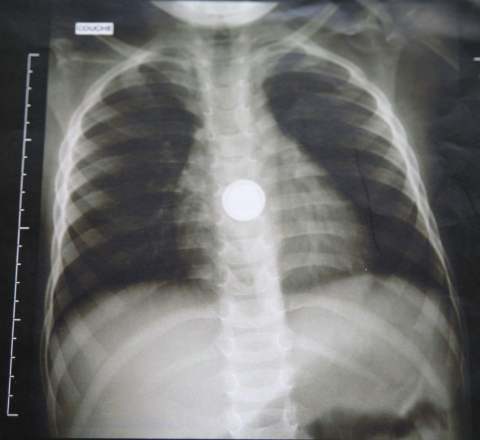

Il faut donc étayer le diagnostic au moyen de l’imagerie. Une radiographie pulmonaire standard de face, si possible en inspiration et expiration forcées, repère facilement un CE radio-opaque (10 % des CE) ; mais ce n’est pas toujours suffisant non plus.

absorption d’une pile bouton vue à la radio